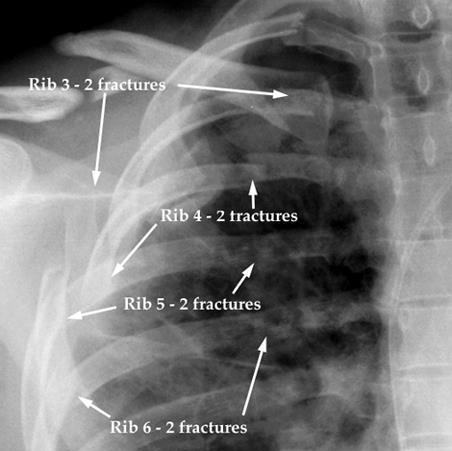

题主提到的右侧4~7肋骨骨折是巧合吗?其实不是的,大多数人肋骨骨折都是4~7肋骨骨折,只不过是左右的分别罢了,这是由我们肋骨的解剖结构决定的。从下图的对比中我们可以看出,第6肋骨是长而薄的,同样在它附近的4~7肋也符合这个特征,所以更容易发生骨折。

而1~3肋骨短粗,且有锁骨、肩胛骨保护,不易发生骨折;8~10肋前端肋软骨形成肋弓与胸骨相连,第11~12肋前端游离,弹性都较大,均不易发生骨折。一旦上述肋骨发生骨折,说明致伤暴力巨大,常合并锁骨骨折、肩胛骨骨折、胸腹腔脏器的损伤,应提高警惕。